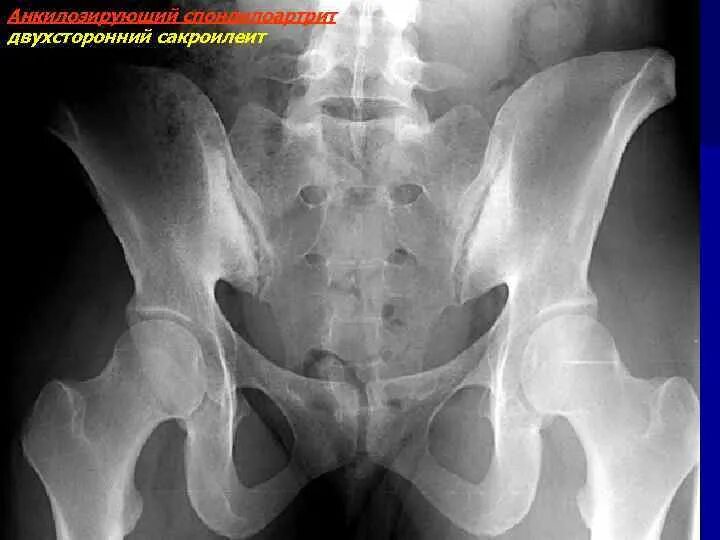

Артрит крестцово подвздошного сочленения